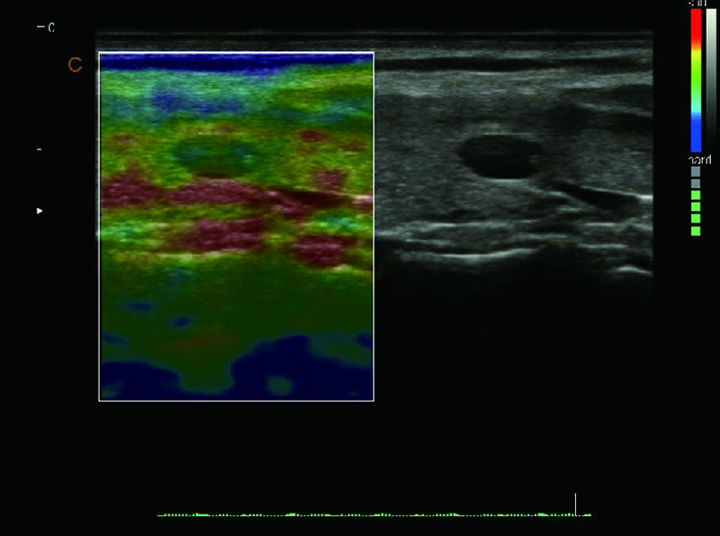

Elastografía Quantitativa